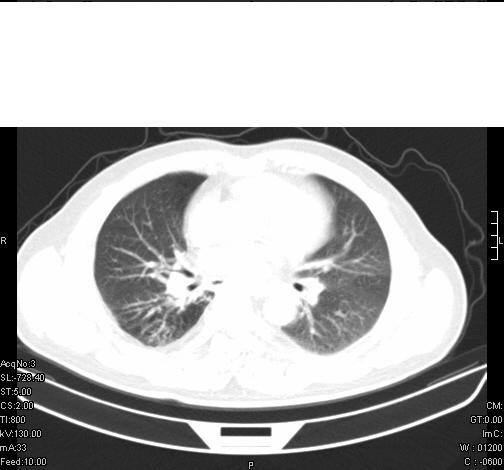

前几天,发了患者的平扫片,患者抗炎一周后增强扫描。右中叶病灶吸收明显,但下叶病灶未见明显吸收。右肺门可见结节影,看来凶多吉少

病灶在下叶,散发,抗炎治疗有效,考虑炎症,楼主说的肺门结节看的不明显

右肺下叶散在的斑片状致密影,下叶支气管变窄。考虑:右肺慢性炎症。

右下肺气管壁增厚,但看不到具体的肿块,还是先考虑炎症,抗炎后复查吧。

第18幅,好像不能简单用炎症解释,前几天我发平扫时,90%人支持肺癌,现在好像大家更倾向于炎症了,我觉得还是不能排除肺癌。